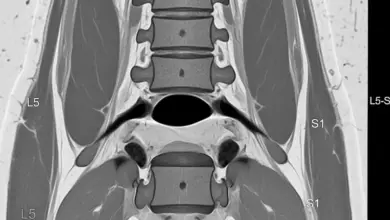

- A radiografia anteroposterior da coluna lombossacra costuma identificar a vértebra de transição.

- A tomografia detalha a anatomia óssea quando necessário.

- A ressonância magnética avalia o disco e sinais de inflamação nas articulações.